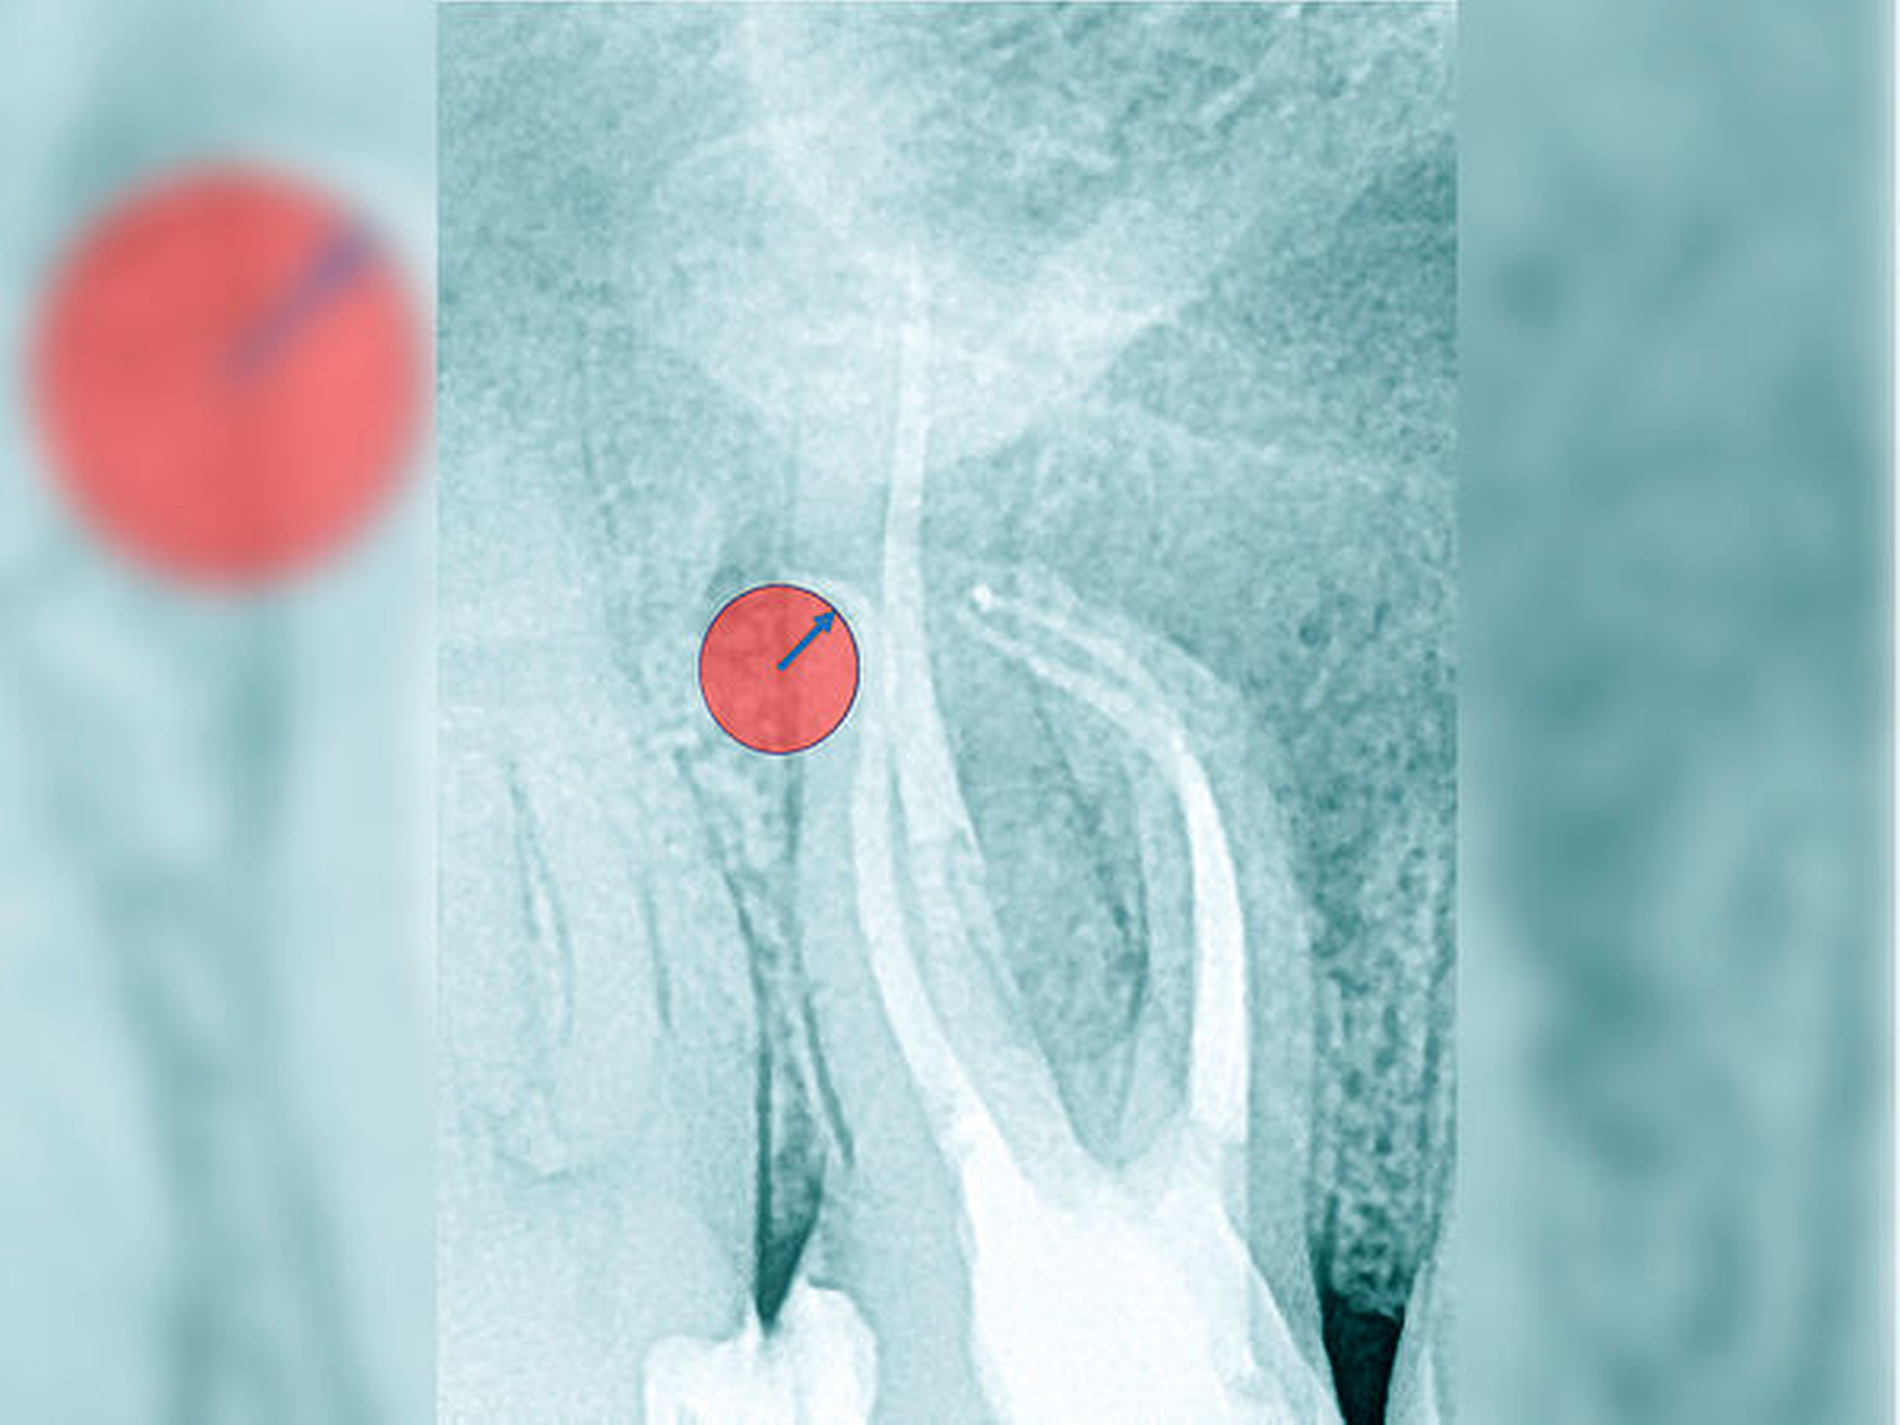

Krümmungsradius: Ist demgegenüber der Verlauf des Wurzelkanals unterbrochen, kann meist mit einer tiefen Wurzelkanalaufteilung gerechnet werden (Abbildung 3) [Reuver, 2002].

Lässt sich der Wurzelkanal auf der Röntgenaufnahme nur apikal erkennen, liegt meist eine Kalzifikation der Pulpa vor, die häufig erst unter Nutzung einer optischen Vergrößerung überwunden werden kann [Kiefner et al., 2017].